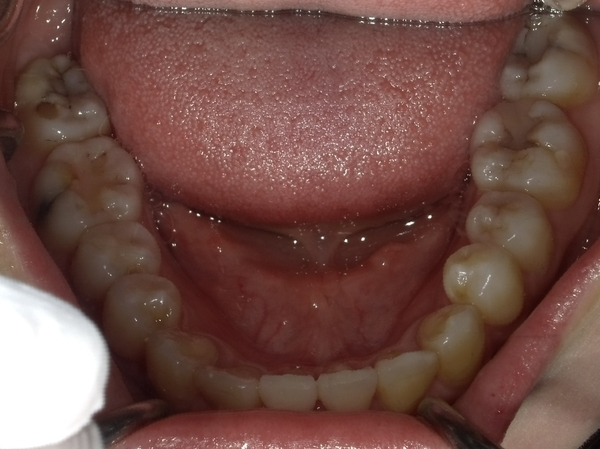

ガタガタとした歯並びや八重歯(叢生)CASE68